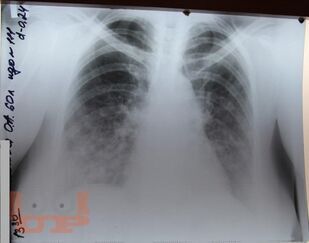

В учебном пособии рассматриваются вопросы терминологии, классификации, диагностики и лечения вирусных пневмоний, их осложнений и ассоциированных с ними патологических состояний. На основании собственного клинического опыта, рекомендаций доказательной медицины, новейшей отечественной и зарубежной литературы представлены материалы по тяжелым и осложненным формам гриппа, острому респираторному заболеванию (ОРЗ) и острой респираторно-вирусной инфекции (ОРВИ), острому бронхиту (ОБ), внебольничной пневмонии (ВП), острому респираторному дистресс-синдрому (ОРДС), сепсису, септическому шоку (СШ) и дыхательной недостаточности (ДН).